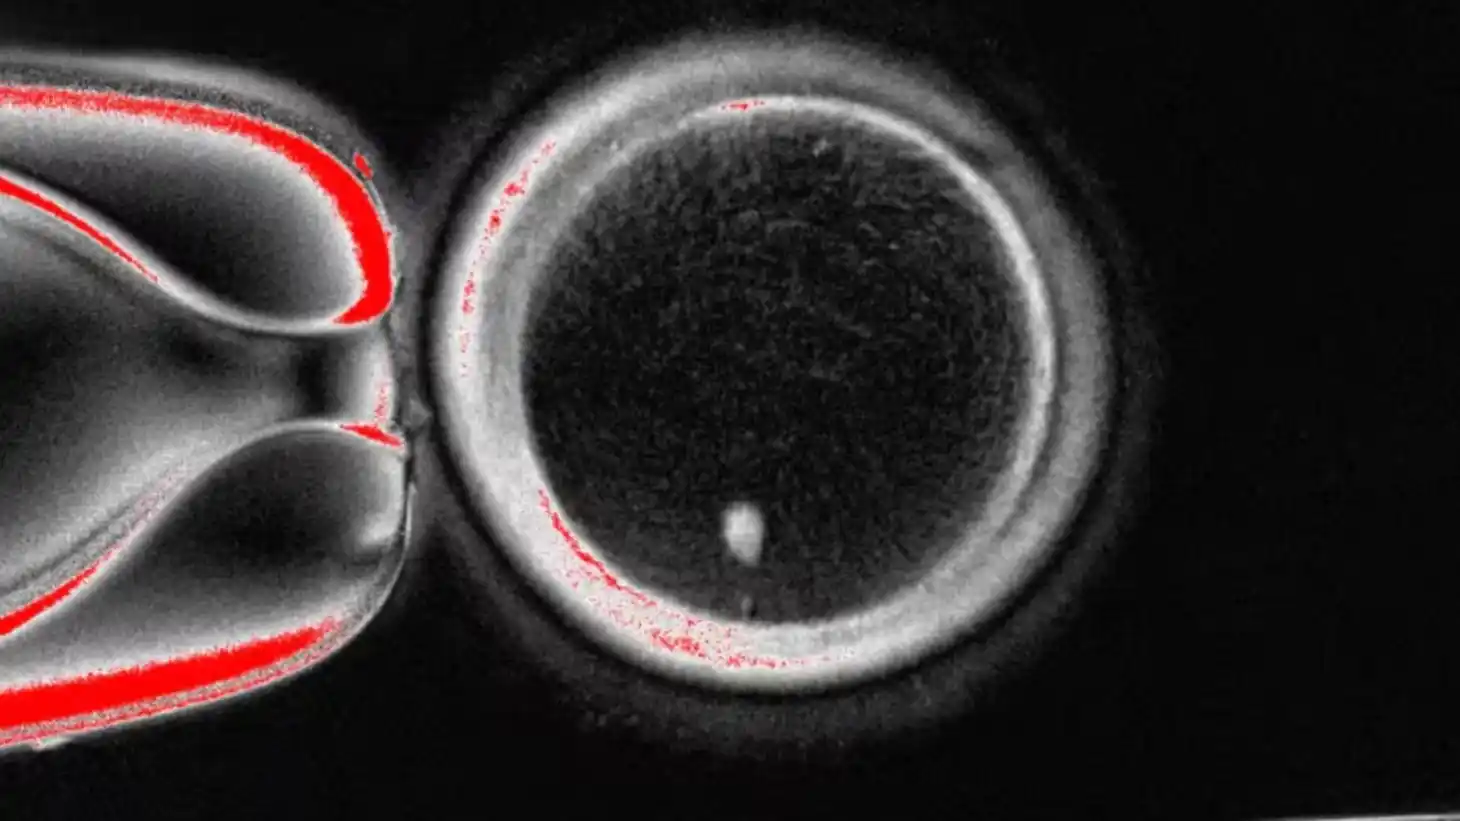

El proceso se basó en la transferencia nuclear de células somáticas, una técnica que consiste en tomar el núcleo de una célula de la piel y colocarlo en un óvulo de donante previamente vaciado de su núcleo. Posteriormente, los investigadores indujeron un proceso denominado “mitomeiosis”, similar a la mitosis, pero diseñado para que la nueva célula redujera su carga genética a 23 cromosomas, como ocurre de manera natural en los óvulos humanos.

El resultado fue la obtención de 82 óvulos con carga genética haploide. De ellos, cerca del 9 % alcanzó la etapa de blastocisto —un estadio temprano del desarrollo embrionario— al ser fertilizados con espermatozoides en el laboratorio.